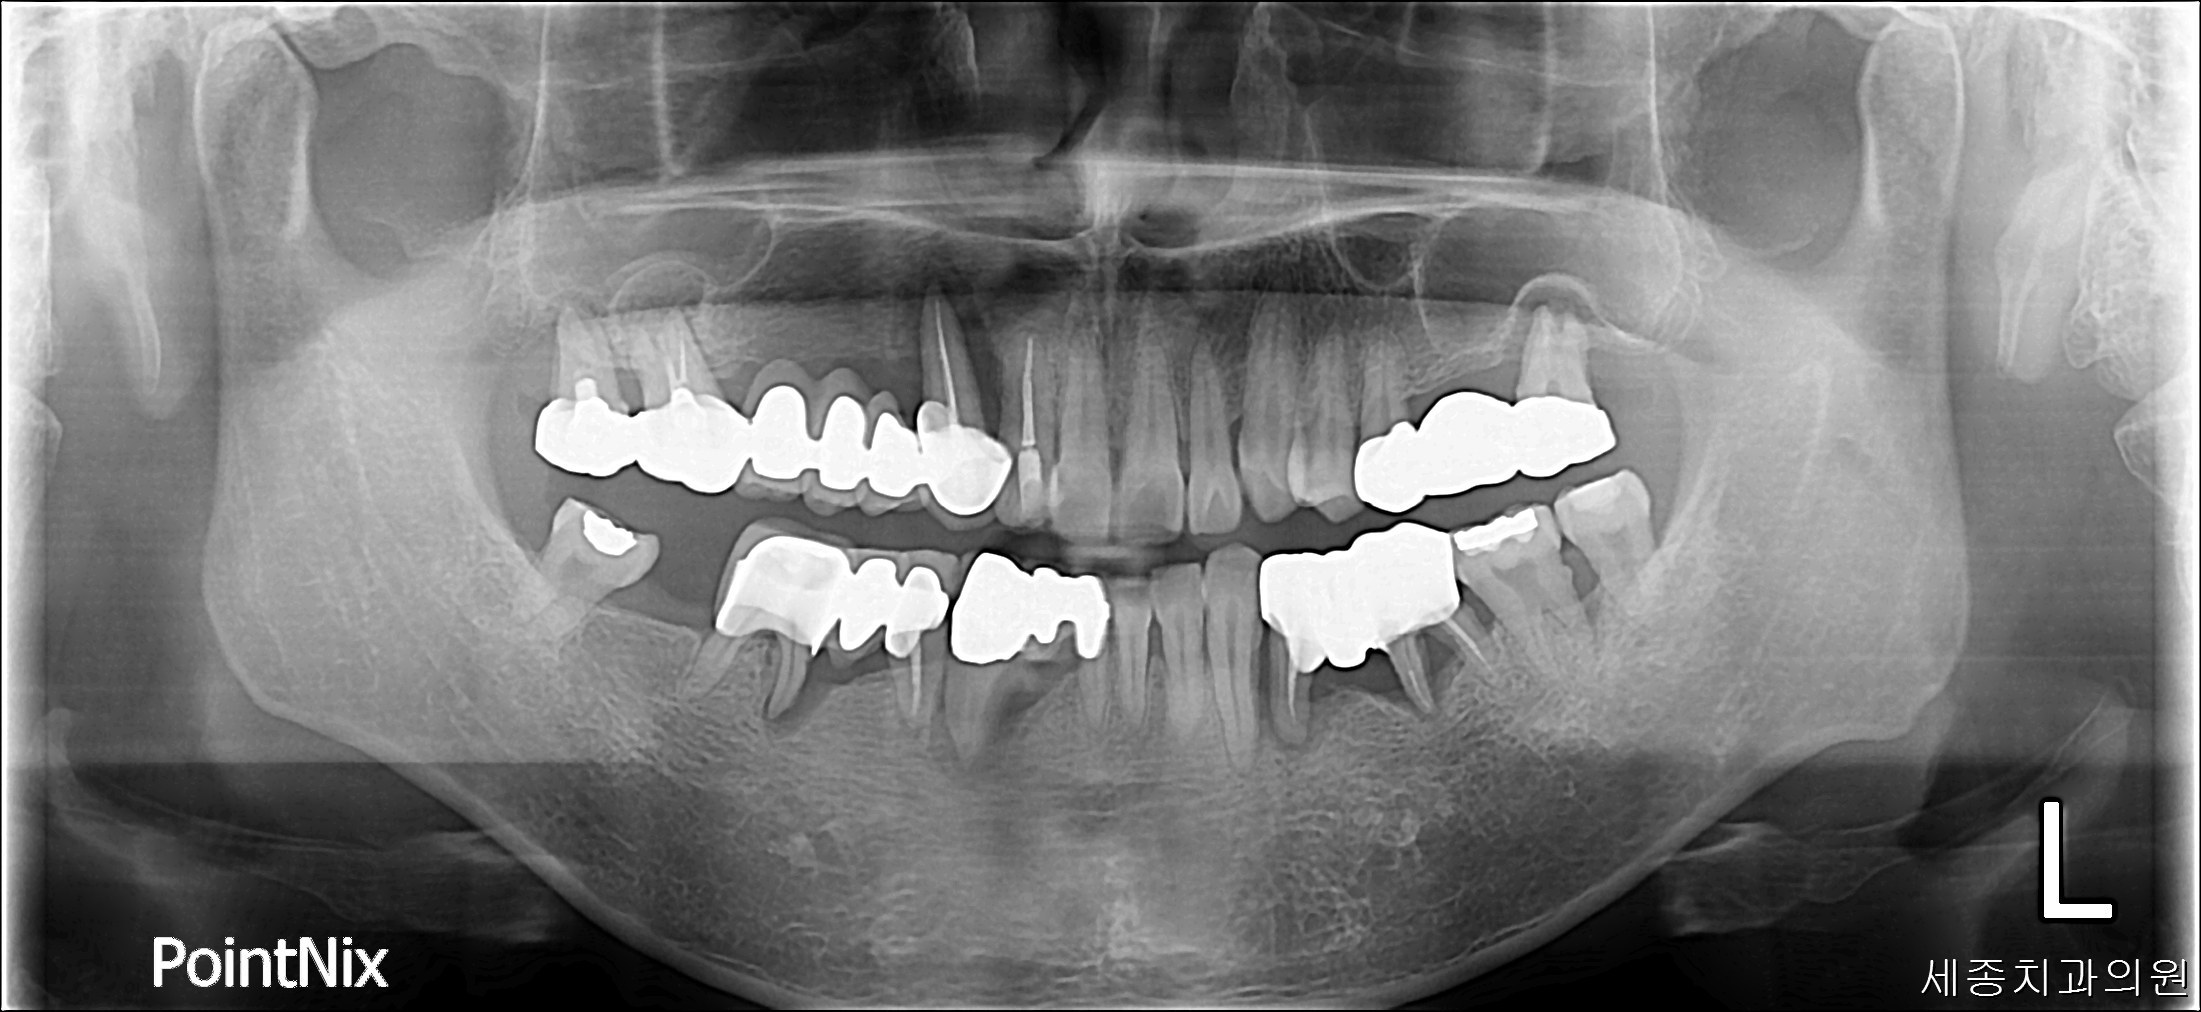

1af20e2354fbb230fca5cc6fbbc70742.jpg

치료전 : 2017-04-06